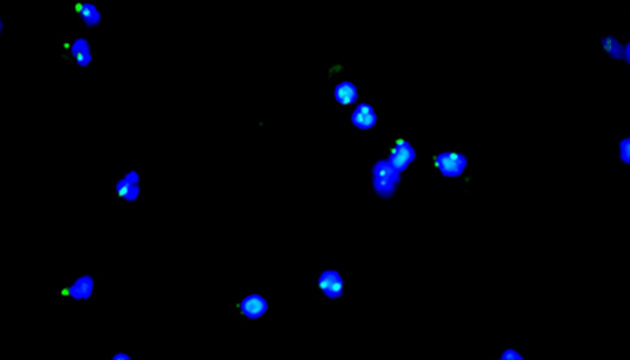

CTC檢測用于上皮腫瘤,如胃腸癌、皮膚癌等。檢測分四步:富集、CD45染白細(xì)胞、CK染CTC、DAPI染核。有DAPI、CK熒光且無CD45熒光,大核細(xì)胞為CTC;有DAPI、CD45熒光為白細(xì)胞。

MF43-N用于CTC檢測